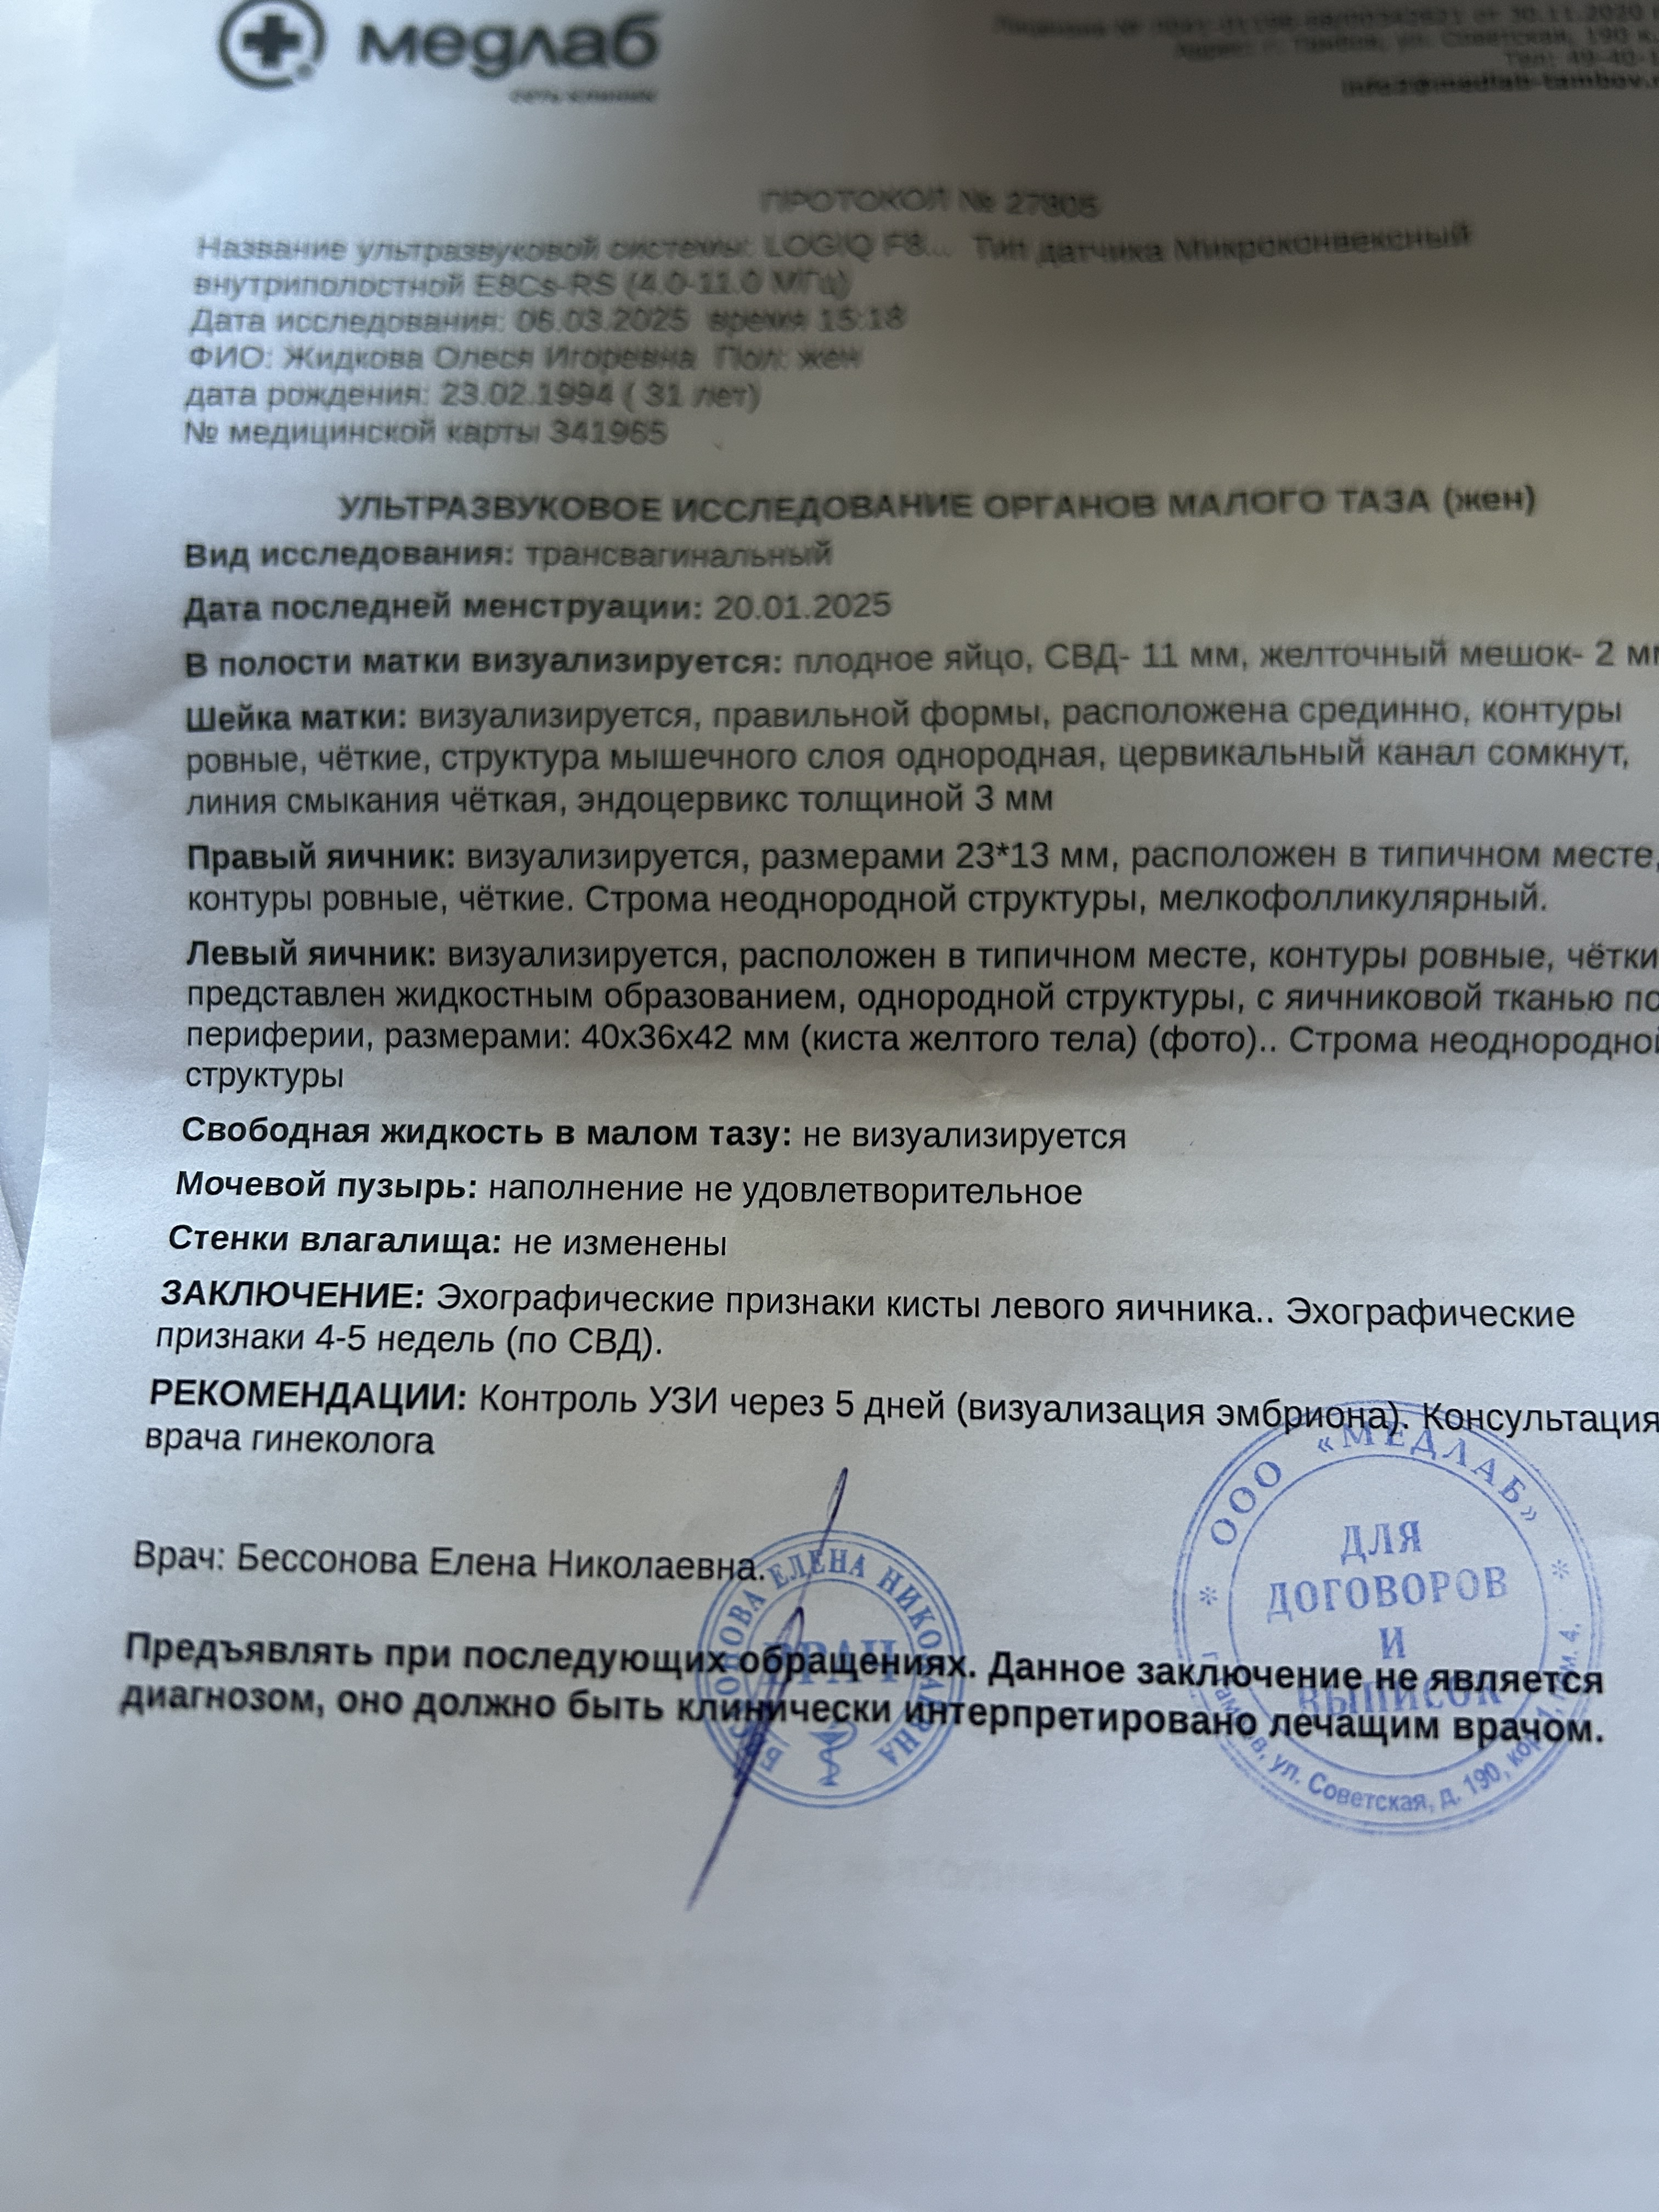

Девочки поделитесь у кого так было и чем это закончилось 🙏🏻Сходила я на узи вчера ,срок по М 6.1 по узи поставили 4-5 недель (фото приложила )ПЯ растет ,появился ЖМ но эмбриона не видно .врачи пугают что там пусто ,отправили гулять еще на 5 дней .Я в дикой панике ,не помню как вышла из клиники и доехала до дома .Не спала всю ночь ,незнаю куда себя деть .Я просто не верю что там все плохо 😓🙏🏻у меня совсем другое чувство .

Сказали если не появится через 5 дней то все на чистку иди а я не верю .а вдруг 😢😢

И что то ПЯ страной формы ,на узи врач про это ничего не сказала ,лишь спросила ничего не беспокоит.